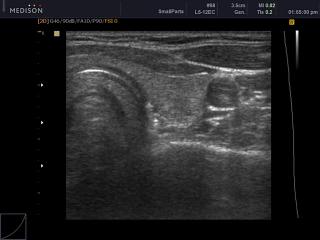

Щитовидная железа, B-режим

SonoAce-X8. Щитовидная железа, B-режим.